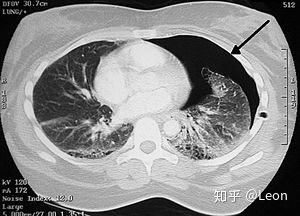

图中是一位右侧气胸患者(图中右面)的电脑断层扫描影像。在胸腔的边缘有着引流管,而图中黑色一片就是邻近于肺膜间(黑)和肋骨(白)的内腔。心脏则在图中央。医学专科胸腔医学、胸腔外科学症状胸痛、呼吸困难、疲劳常见始发于突发性肇因未知、创伤风险因子慢性阻塞性肺病(COPD)、结核病、抽烟诊断方法胸部X光、超声波、电脑断层扫描相似疾病或共病肺部大疱、血胸预防禁烟或戒烟治疗保守治疗、空针穿刺、胸管置放、肋膜黏连术盛行率约每10万人中20例外伤性气胸。